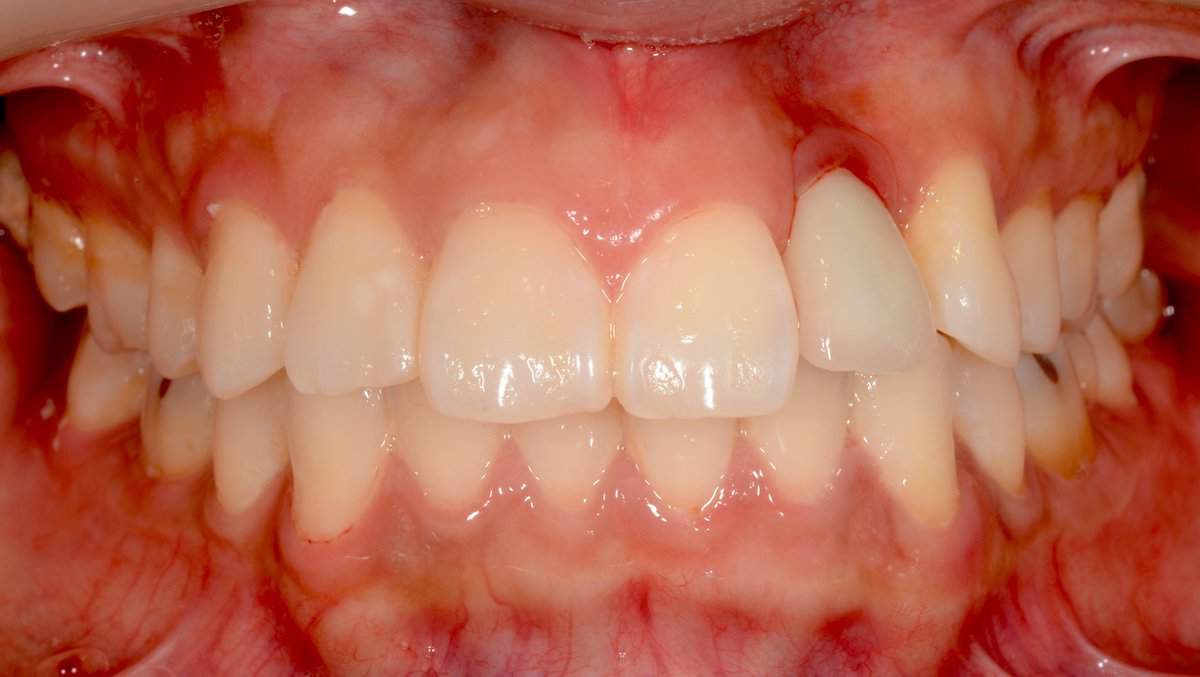

Established Mucositis and swelling buccal of the 22, initially attributed to absence of keratinised mucosa and thus referred for soft tissue augmentation. Studying the CBCT however, in combination with the clinical examination, one can see the main problem here to be the implant position. In particular the bucco-palatal angle results in the implant shoulder  being too buccal. As a result the cement retained prosthesis is also protruding in its apical part, resulting to recession beyond the mucogingival line. Unless we can correct the implant position and the crown, any intervention targeting the soft tissues alone is likely to make the problem even worse.